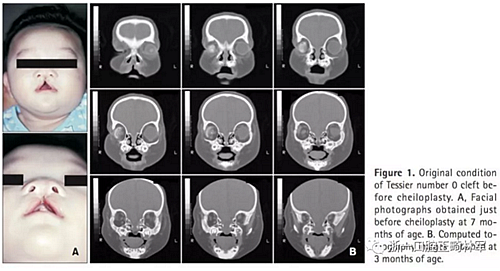

患者信息(圖1):

5歲Tessier0號面裂伴右側(cè)小眼畸形。病史如下:1月起右側(cè)佩戴義眼,7月行唇裂修復(fù)術(shù),1歲11月時(shí)行腭成形術(shù)(V-Y),7歲7月時(shí)行髂骨移植術(shù),8歲10月時(shí)摘除畸形眼球后植入人工植體,10歲1月時(shí)行額部懸吊及各項(xiàng)眼瞼整形手術(shù)。